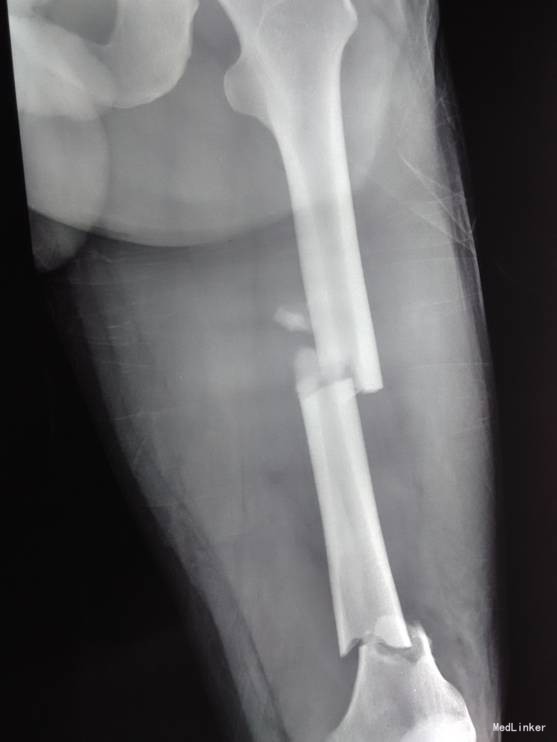

患者自诉于2014-6-1中午骑摩托车被汽车撞翻,伤后昏迷,被肇事司机寄送到当地医院,拍片检查,诊断为:颅脑损伤,脾破裂,左股骨骨折,左胫骨平台骨折。给予保守治疗,并转往盖州市中心医院,急诊下行脾切除术,右下肢给予石膏固定,待患者病情稳定后建议转往上级医院。现患者为求进一步诊治来我院就诊,以“左股骨骨折,左胫骨平台骨折,颅脑损伤,脾切除术后”为主要诊断收入我科。患者伤来无恶心呕吐,腹痛腹胀,胸闷心悸等特殊不适,饮食差、睡眠可,小便可,未大便,体重无明显变化。

诊断:左股骨骨折,左胫骨平台骨折 双侧胸腔积液 脑出血 脾切除术后 患者入院后见患肢肿胀明显,给予患肢抬高位,冷敷,甘露醇消肿等对症治疗,带患肢出现褶皱试验阳性后,全麻下行右股骨干骨折闭合复位髓内针固定术;左胫骨平台骨折切口复位钢板内固定术,术后患者肿胀明显,给予抗炎,消肿,冷敷,患肢抬高等对症治疗。患者每天换药观察切口愈合情况,无红肿及渗出,待伤口14天后予以拆线治疗,予以出院,给予康复处方。